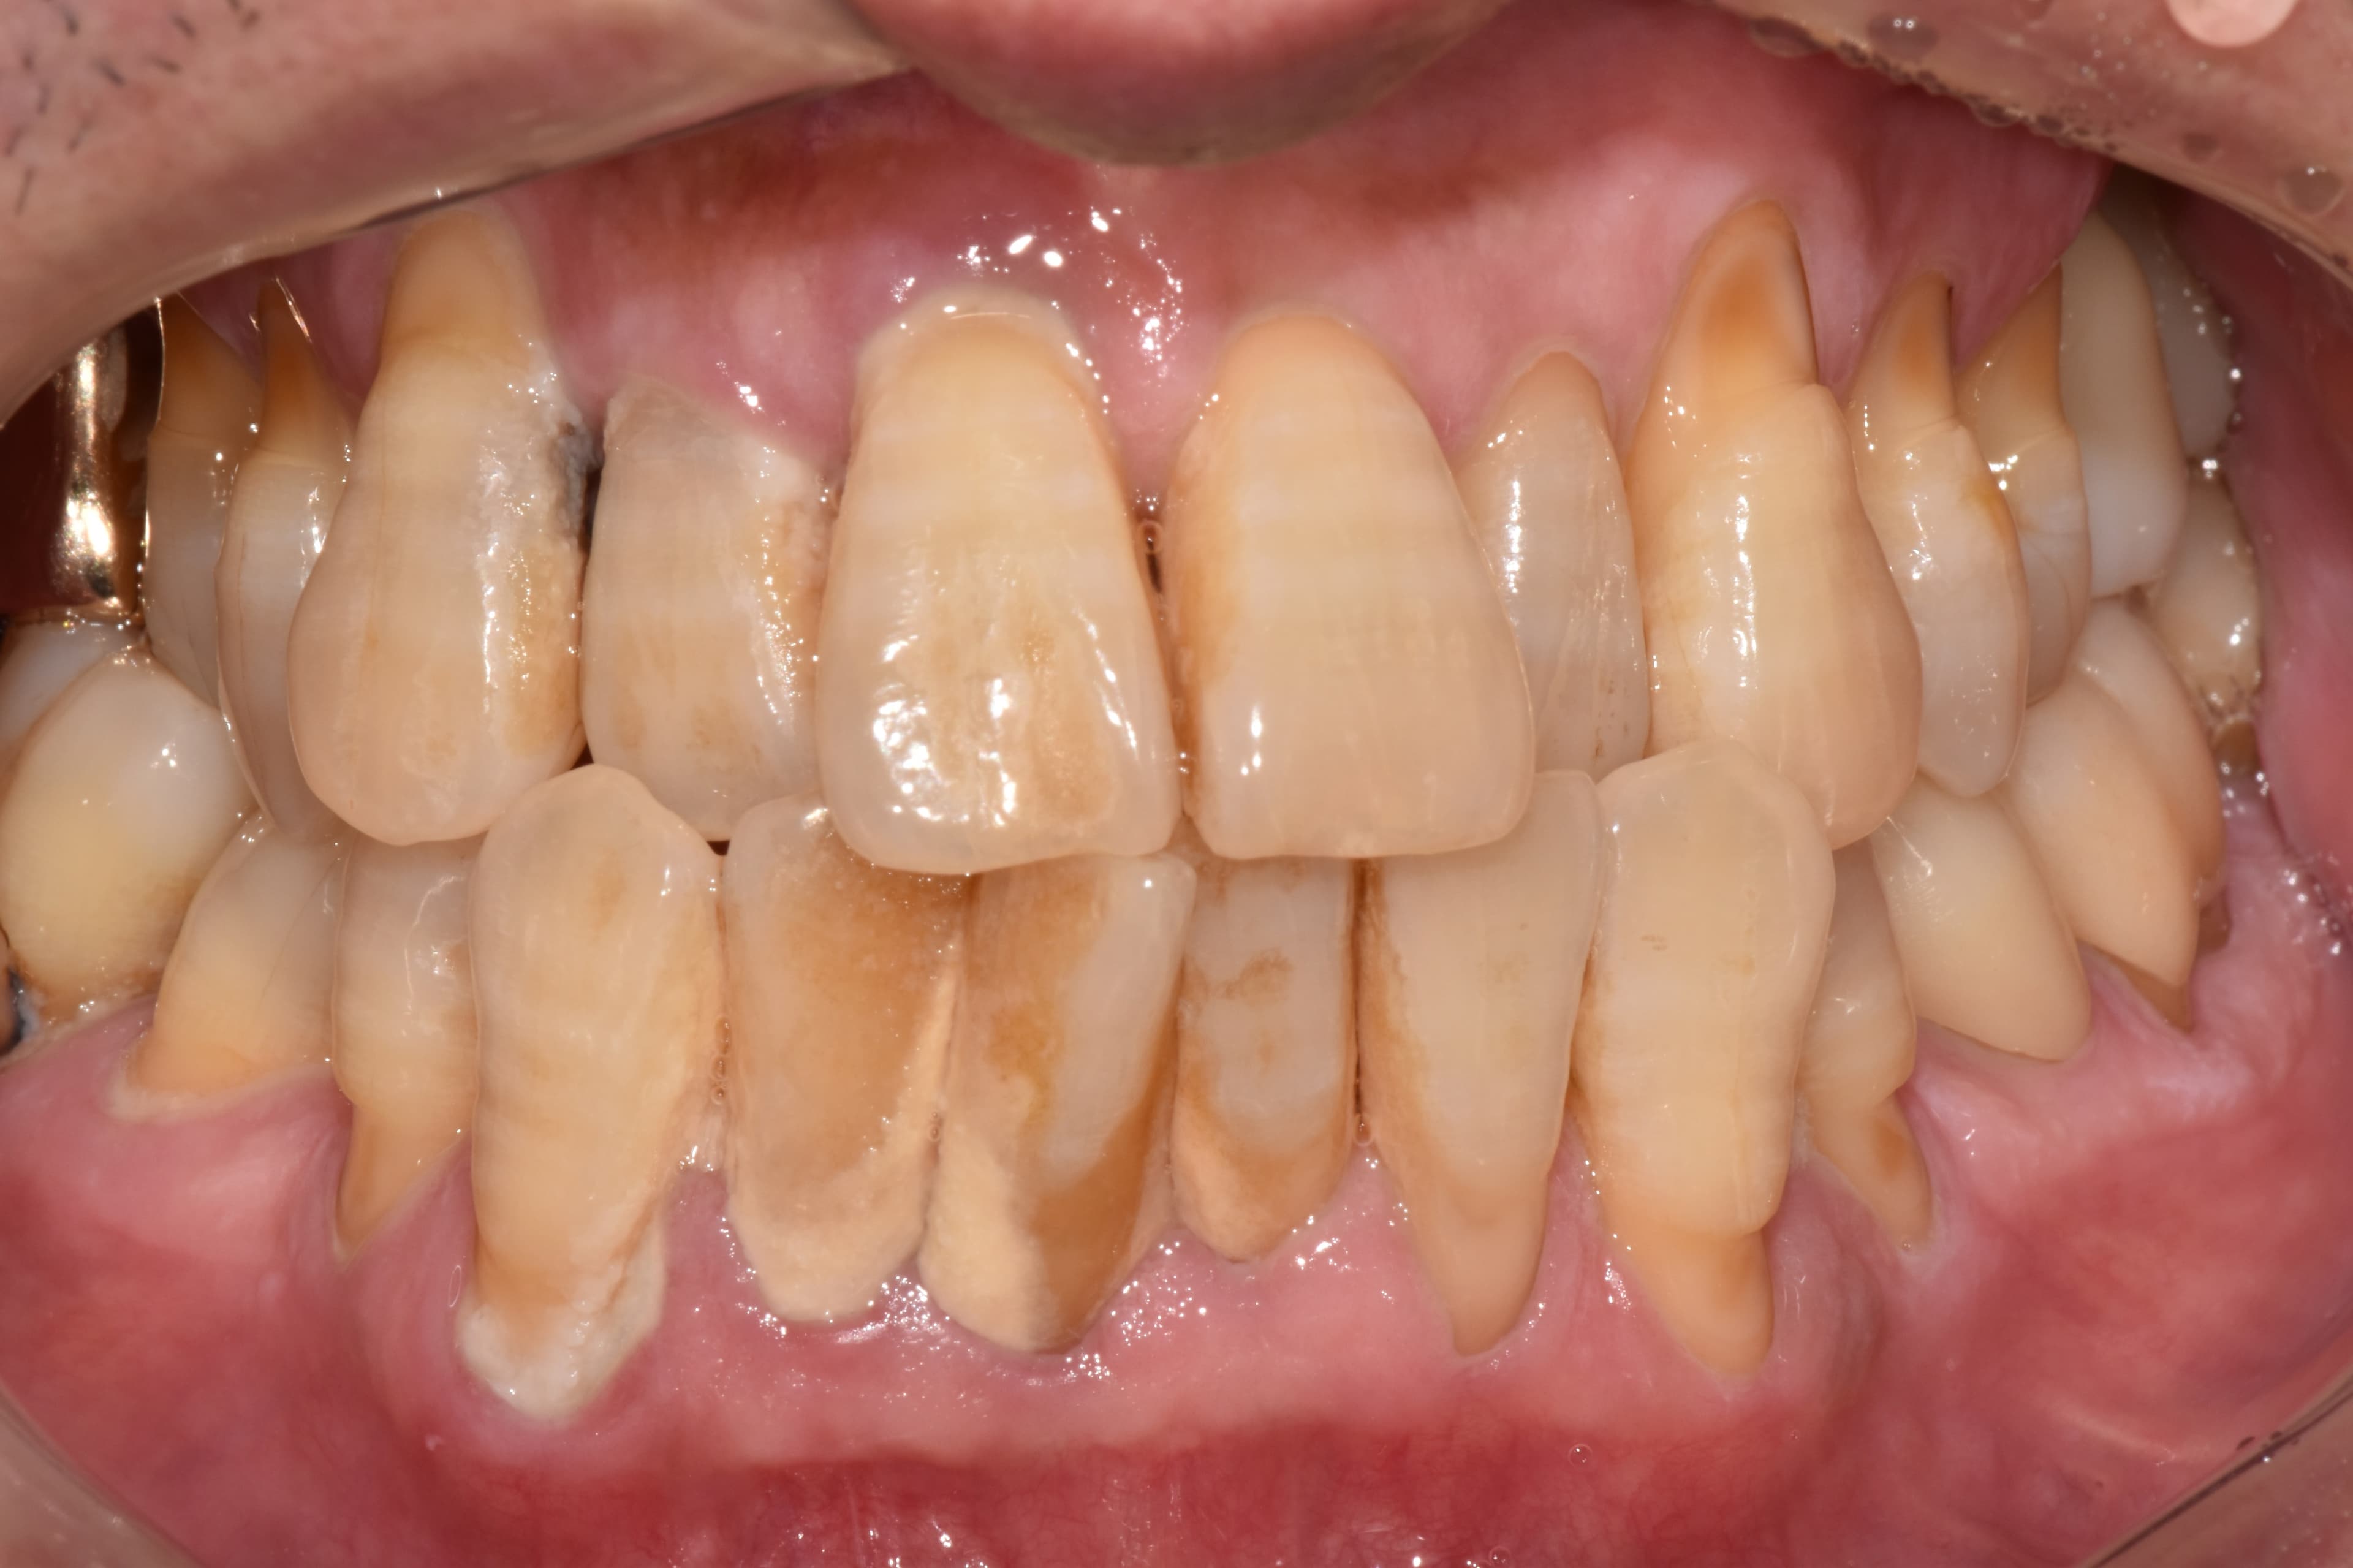

실제 치료 사례

정기적인 잇몸 치료로 임플란트 없이 건강한 치아 유지

"정기적인 관리 덕분에

50대에도 모든 치아가 건강해요"

Before

After

치석과 잇몸 염증이 심했던 상태

정기적인 스케일링과 관리로 건강하게 유지